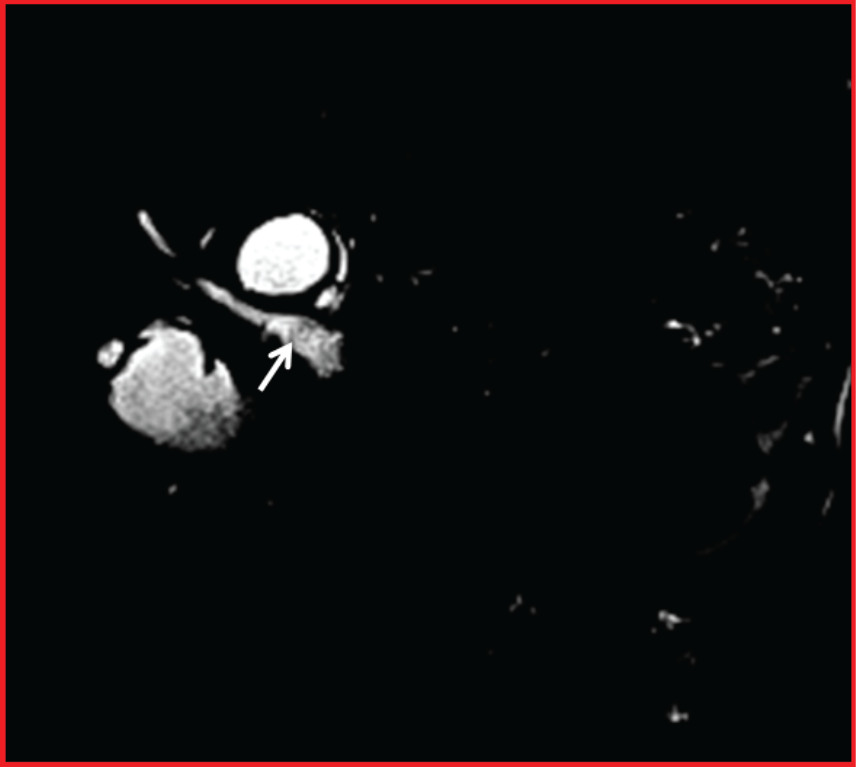

A 69-year-old man was admitted to our department with a 2-day history of jaundice, nausea, and vomiting. MRCP showed that dilatation of the intra and extrahepatic bile ducts and fragmented membranes in the common biliary duct (Figure 1). Additionally, a hydatid cyst which is lost of volume tension was detected in segment 6 of liver (Figure 2). Impaction of hydatid material into the common bile duct was relieved endoscopically.

Figure 2: Axial T2 weighted image shows a hydatid cyst lesion with decreased volume and lobulated contour in the segment 6 of the liver (white arrow).